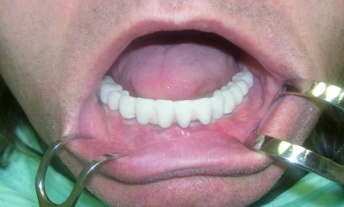

Metoda All-on-four

Bezzubá čelist je hlavní indikací pro ošetření pomocí implantátů. Zejména celkové zubní náhrady v dolní čelisti mají velice nízkou stabilitu a držení díky velkému úbytku kosti.

S pomocí zubních implantátů můžeme díky různým kotevním systémům (třmeny, kulové hlavy, Locatory) zajistit stabilitu a držení protézy nebo při použití většího počtu implantátů zhotovit pevné náhrady – můstky nalepené nebo našroubované na pevno na implantáty.

S těmito typy náhrad můžeme dosáhnout perfektní funkci, výbornou estetiku, fonetiku a současně zajistit u pacienta možnost dobré hygienickou péče a čištění, která je pro životnost implantátů velice důležitá.